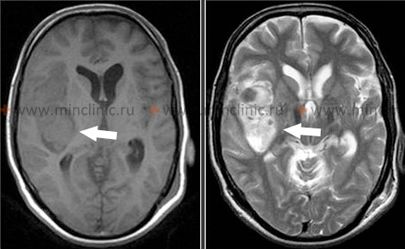

თალამუსის ჰიპერტენზიული ინტრაცერებრული სისხლჩაქცევები

თალამუსში (ჰიპერტენზიული სისხლდენების კიდევ ერთი ხშირი ლოკაცია) დაწყებული სისხლჩაქცევა, როგორც წესი, იწვევს კონტრალატერალურ ჰემიპლეგიას ან ჰემიპარეზს მიმდებარე შიგნითა კაფსულის კომპრესიის ან ჩართვის გამო [1, 2]. გამოხატული თვისება ხშირად არის მგრძნობელობის კონტრალატერალური ნახევრად დაკარგვა (ჰემისენსორული დანაკარგი), რომელიც გავლენას ახდენს ყველა სენსორულ მოდალობაზე (ტკივილი, ტემპერატურა, პროპრიოცეფცია, ტაქტილური შეგრძნება), რაც ასახავს თალამუსის, როგორც მთავარი სენსორული გადამრთველი ბირთვის, როლს [1].

დომინანტური ნახევარსფეროს თალამუსის დაზიანებებმა შეიძლება გამოიწვიოს ენის/მეტყველების დარღვევები (დისფაზია ან აფაზია), რაც ხშირად ხასიათდება გამართული მეტყველებით პარაფაზიული შეცდომებით, მაგრამ შედარებით შენარჩუნებული გამეორების უნარით, ზოგჯერ თან ახლავს მეხსიერების დეფიციტი [1]. სისხლჩაქცევამ არადომინანტურ თალამუსში შეიძლება გამოიწვიოს კონსტრუქციული აპრაქსია და სივრცითი უგულებელყოფა (აპრაქტოაგნოზია) [1]. ჰომონიმური მხედველობის ველის დეფექტები (გავლენას ახდენს მხედველობის ველის ერთსა და იმავე ნახევარზე ორივე თვალში) შეიძლება მოხდეს თალამუსის მახლობლად მდებარე გზების ჩართვის გამო, მაგრამ შეიძლება ნაწილობრივ გაუმჯობესდეს [1]. თალამური სისხლჩაქცევის გავრცელება ინფერომედიალურად სუბთალამური რეგიონისა და შუა ტვინის ზედა ნაწილისკენ ხშირად იწვევს დამახასიათებელ ოკულომოტორულ (თვალის მოძრაობის) დისფუნქციებს, მათ შორის [1]:

- ვერტიკალური მზერის დარღვევა (განსაკუთრებით ზევით მზერის პარეზი)

- თვალების ქვემოთ დევიაცია მოსვენებულ მდგომარეობაში ("ჩამავალი მზის სიმპტომი")

- გუგის პათოლოგიები: ანიზოკორია (არათანაბარი გუგები), გუგები ხშირად მცირე ან საშუალო ზომისაა და სუსტად რეაგირებენ სინათლეზე

- Skew დევიაცია (თვალების ვერტიკალური ასიმეტრია)

- დარღვეული კონვერგენცია

- ფსევდო-აბდუცენსის პარეზი (დარღვეული თვალის გარეთ მოძრაობა, რომელიც ბაძავს მეექვსე ნერვის პარეზს მზერის გზების ჩართვის გამო)

- რეტრაქციული ნისტაგმი (ზევით მზერის მცდელობისას თვალები იწევს უკან ბუდეებში)

სხვა პოტენციური ნიშნები მოიცავს იპსილატერალურ პტოზს და მიოზს (ჰორნერის სინდრომის ნაწილი, თუ სიმპათიკური გზები კომპრესირებულია), ქუთუთოს შეშუპებას ან იშვიათად, მუტიზმს (საუბრის უუნარობას), განსაკუთრებით ორმხრივი ან დომინანტური თალამუსის ჩართვისას [1].

თავის ტვინის კომპიუტერული ტომოგრაფია (კტ), კერძოდ უკონტრასტო კტ, არის ძალზე საიმედო და ფართოდ ხელმისაწვდომი მეთოდი მწვავე ინტრაცერებრული სისხლჩაქცევის დიაგნოსტირებისთვის [4, 5]. ახალი სისხლი ჩანს ჰიპერდენსიულად (კაშკაშა თეთრი) კტ სკანირებაზე, რაც მას ადვილად იდენტიფიცირებადს ხდის [4]. კტ-ს შეუძლია საიმედოდ აღმოაჩინოს 1 სმ ან მეტი დიამეტრის ჰემორაგიული დაზიანებები თავის ტვინის ნახევარსფეროებსა და ნათხემში, განსაკუთრებით მაშინ, როდესაც შესრულებულია სიმპტომების დაწყებიდან პირველი რამდენიმე დღის განმავლობაში [4]. დროთა განმავლობაში (ტიპურად ერთი-ორი კვირის შემდეგ), ჰემატომის სიმკვრივე (ატენუაცია) თანდათან მცირდება სისხლის პროდუქტების დაშლასთან ერთად, საბოლოოდ ხდება იზოდენსიური (თავის ტვინის ქსოვილის მსგავსი სიმკვრივე) და მოგვიანებით ჰიპოდენსიური (ტვინის ქსოვილზე მუქი) [4]. ეს ნიშნავს, რომ ძველი სისხლჩაქცევები შეიძლება გამოგვრჩეს კტ-ზე, თუ არ არის ნარჩენი პერიფოკალური შეშუპება ან მას-ეფექტი [4]. ზოგიერთ შემთხვევაში, კონტრასტირების რგოლი შეიძლება გამოჩნდეს გაწოვის სტადიაში მყოფი ჰემატომის გარშემო 2-4 კვირის შემდეგ, რომელიც შენარჩუნდება რამდენიმე თვის განმავლობაში, რამაც შეიძლება ზოგჯერ მოახდინოს სიმსივნის ან აბსცესის იმიტაცია [4]. როგორც ადრე აღვნიშნეთ, ხიდში ან უკანა ფოსოს სხვა სტრუქტურებში მცირე სისხლჩაქცევების ვიზუალიზაცია ზოგჯერ შეიძლება რთული იყოს კტ-თი პოტენციური მოძრაობის არტეფაქტებისა და მიმდებარე ძვლისგან გამოსხივების გამკვრივების (beam-hardening) არტეფაქტების გამო [4].

თავის ტვინის მრტ ზოგადად უფრო მგრძნობიარეა, ვიდრე კტ, მცირე ჰემატომების გამოსავლენად, განსაკუთრებით ტვინის ღეროში (ხიდი და მოგრძო ტვინი), და სხვადასხვა ეტაპზე (ზემწვავე, მწვავე, ქვემწვავე, ქრონიკული) სისხლჩაქცევების დასახასიათებლად სხვადასხვა რეჟიმებზე (როგორიცაა T1, T2, FLAIR, გრადიენტული ექო/SWI) სისხლის დაშლის პროდუქტების სიგნალის მახასიათებლების საფუძველზე [4]. თუმცა, ზემწვავე სისხლჩაქცევის (პირველი რამდენიმე საათი) დიფერენცირება სხვა მდგომარეობებისგან ზოგჯერ შეიძლება რთული იყოს მრტ-თიც კი, და კტ რჩება პირველად ინსტრუმენტად მწვავე პირობებში სისხლჩაქცევის სწრაფი გამორიცხვისთვის [4, 5].